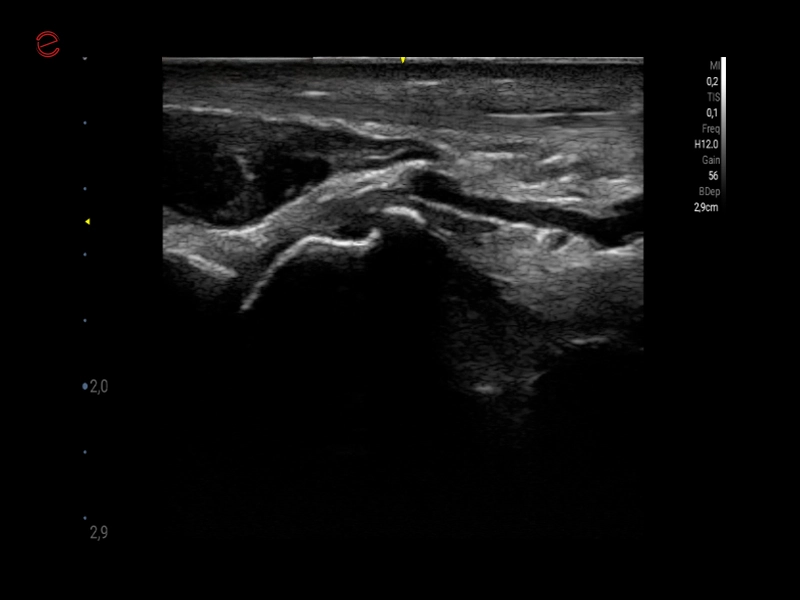

MyLab™9 Platform - Very-superficial linear imaging with Power Doppler algorithm

MyLab™9 Platform - Very-superficial linear imaging with Power Doppler algorithm